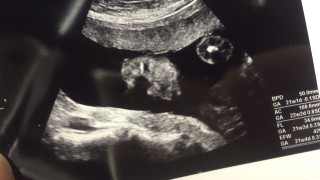

前回多分女の子だと言われ、今回は間違いなく女の子だねと言われました。 推定体重467g、週通りの大きさです♪

重さは441g

前回はうつ伏せだったけど、今回ははっきり!

高い鼻がパパそっくり!女の子の再確認とりました★